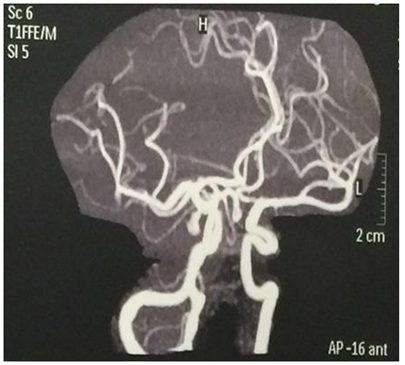

Female patient, 51 years old, brown, born in Juazeiro, Ceará. There was a month with progressive headache, pulsatile type in fronto-temporal region and right retro-ocular. In a few days, the right palpebral ptosis and hyperalgesia in V1 topography were added to the headache. Use of analgesics without clinical improvement ("the pain was so intense that she considered the possibility of suicide"). Absence of history of aneurysm and systemic diseases in the family. Deny contraceptive use. At physical examination: regular general condition, painful fascia, afebrile, atypical gait, eudychokinesis, right palpebral ptosis, as shown in Figure 1, consensual photoreagent, right mydriasis, as shown in Figure 2, hyperalgesia in V1 topography, strabismus divergent, as shown in Figure 3 & 4, and photophobia. Angiography confirmed the presence of sacculate aneurysm of the posterior communicating segment of the right internal carotid artery, as shown in Figure 5, also confirmed by magnetic resonance and magnetic resonance angiography, as shown in Figure 6 & 7. During the surgical procedure it was confirmed that the aneurysm dissected the cavernous sinus. However, it was observed that, instead of the lateral aneurysm in contact with the third cranial pair in the temporal, which is the habitual one, it made a medial orientation in contact with this in the cavernous sinus, due to the conformation of the aneurism in the form of hammer.6 This can also be justified by the fact that the posterior communicating artery in this case has no fetal pattern and the caliber of it is inferior to the posterior cerebral artery branch P1.6 In this way, it leaves the internal carotid artery in a more medial orientation.6 In the postoperative period there was an improvement in pain, but palpebral ptosis on the right, divergent strabismus, consensual photoreagent, fixed right mydriasis and photophobia persisted. Control angiography showed absence of residual aneurysm in the posterior communicating segment of the right internal carotid artery. Figure 8 shows the clipping of the region involved in the postoperative period.

Figure 6 Magnetic resonance angiography showing correlated aneurysm.